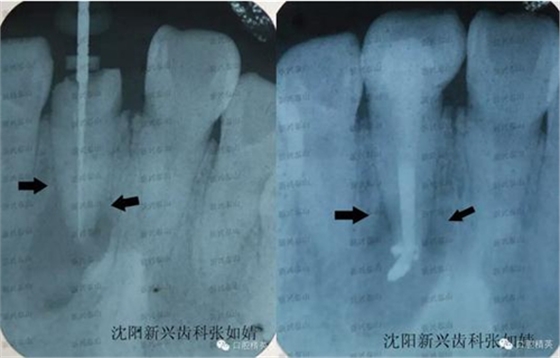

戴牙后拍了一張X線片,根管治療一個(gè)月了,我想看下他牙根炎癥是否有所好轉(zhuǎn)。

真實(shí)的蛻變----熱牙膠根管充填之后的牙冠修復(fù)真實(shí)的蛻變----熱牙膠根管充填之后的牙冠修復(fù),左圖為治療時(shí)確定牙根長(zhǎng)度是否準(zhǔn)確時(shí)拍的X線片,右圖為戴牙之后X線影像,右圖牙齒有些拉長(zhǎng)了。

兩圖對(duì)比,注意箭頭指向處距根尖的位置,治療后炎癥區(qū)域,即根尖的大面積陰影,有好轉(zhuǎn)的跡象,陰影的邊緣開始向根尖縮聚。由于炎癥太重,根尖此處的病灶要慢慢吸收,是一個(gè)過程,治療一個(gè)月時(shí)間,已好轉(zhuǎn)很多,長(zhǎng)期追蹤這個(gè)患者的病情,定期復(fù)診,觀察病灶區(qū)域的變化,及時(shí)掌握牙齒情況。

從右圖顯而易見的,牙冠修復(fù)體的透光度和鄰牙非常接近,沒有形成低密度阻射的影像。